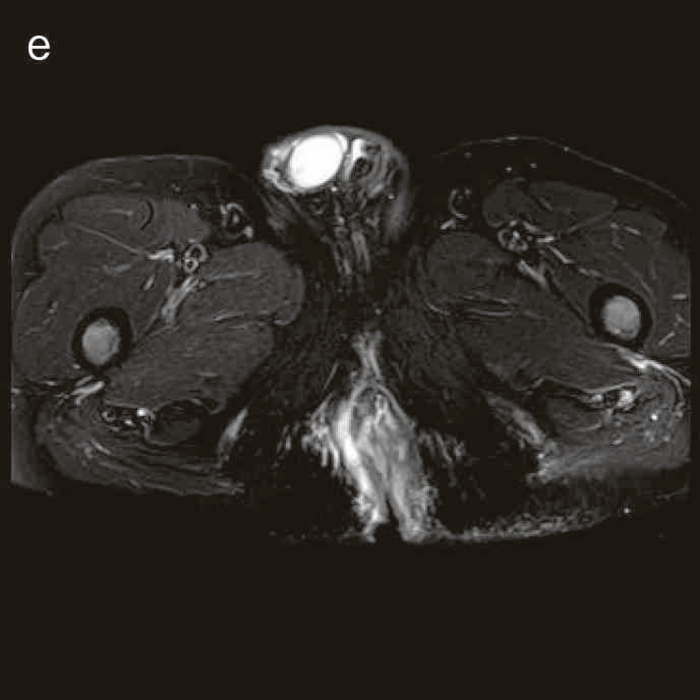

図38 骨盤部MRI

術前の骨盤部MRIでは右側の痔瘻瘻管と,左側の瘻管,周囲のリンパ節腫大を認めた。

明らかな癌を示す所見は不明であった。

診断時のMRIでは直腸下部壁内から周囲にhigh intensity areaが拡がり,右側には痔瘻の瘻管を認めた。high intensity areaは前方で前立腺や陰茎海綿体付近まで広がっていた。